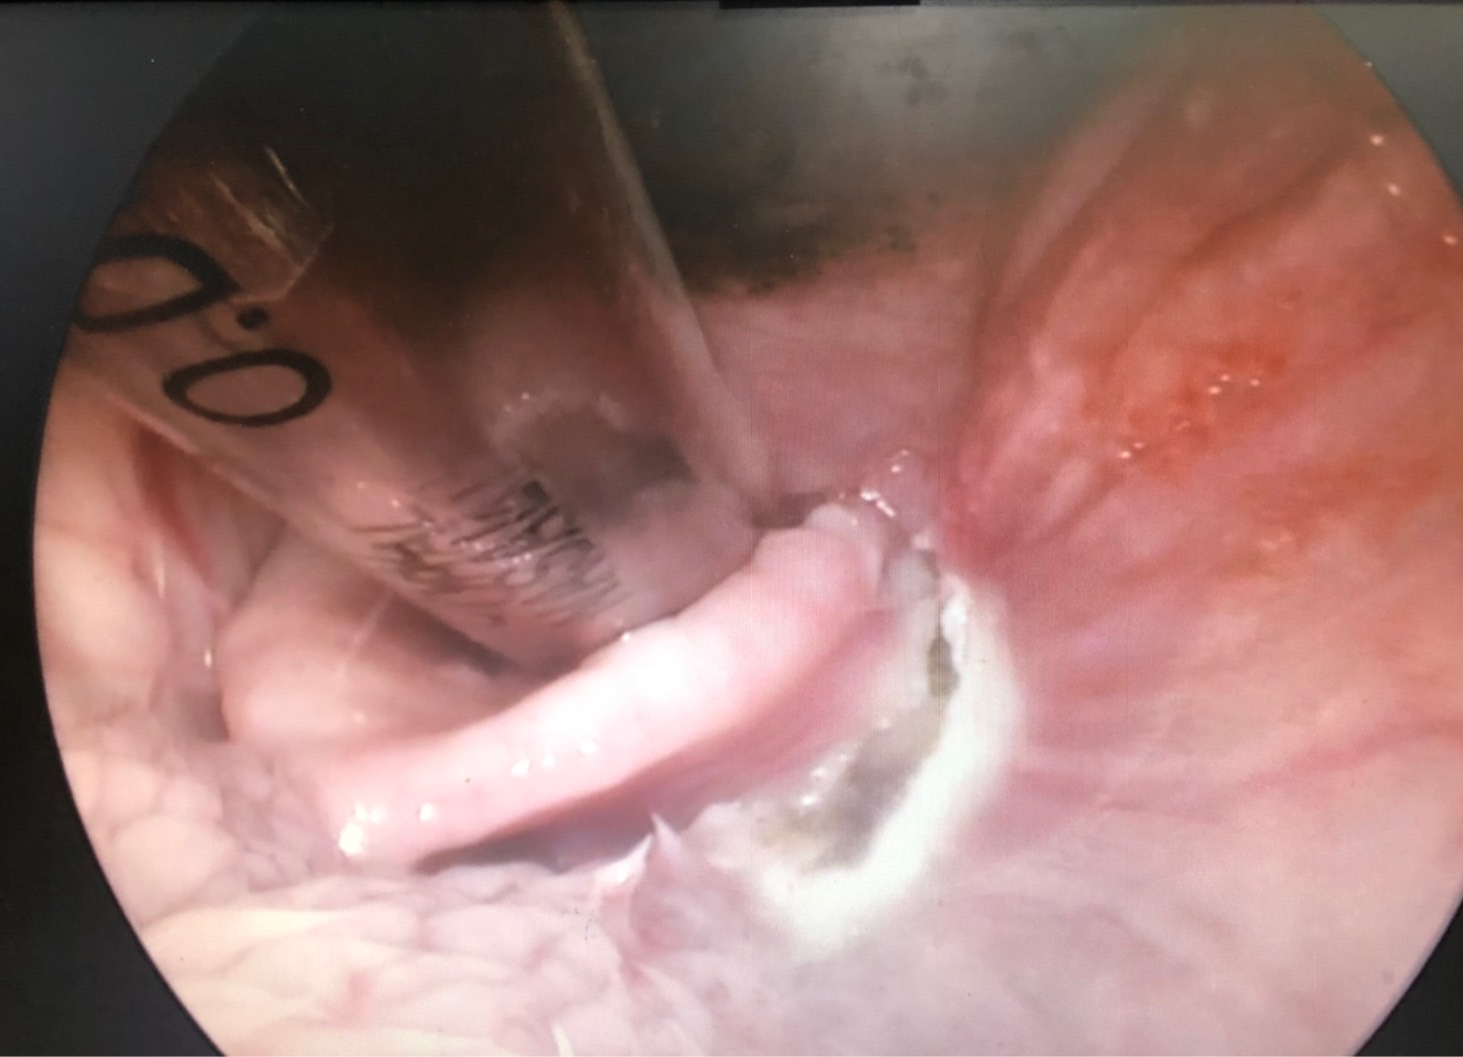

初步懷疑呼吸道阻塞,安排電腦斷層掃描/內視鏡探查手術,精準定位病灶團塊的範圍,

利用內視鏡輔助套環套住團塊後經電燒將可見到範圍盡量切除乾淨。

病理報告為嚴重、慢性活躍性、漿細胞及化膿性喉炎,伴隨肉芽組織生成及局部上皮細胞異型性,會厭旁團塊